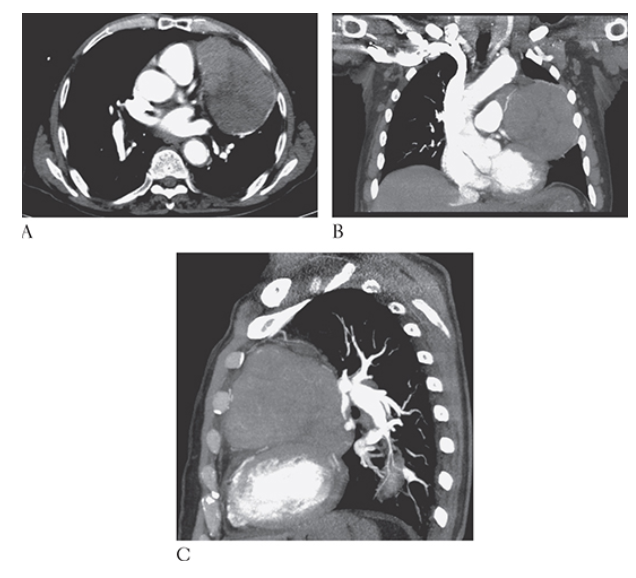

What is A

Thymoma. Axial coronal MPR

What is B

Thymoma. Axial and sagittal MPR

What is C

Thymoma. Axial CECT images show a large lobulated mass within the left anterior mediastinum. This was found to be a mixed lymphoepithelial thymoma at surgery.